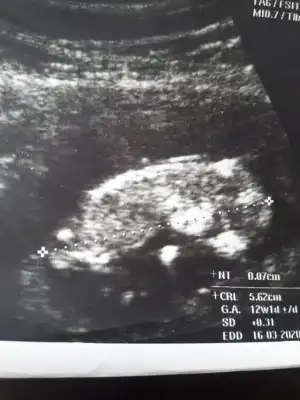

11 yada 12 hafta olmalı nub için kafa şekli erkek gibi ama tutmayabilir siz 11 yada 12 hafta usg paylaşın